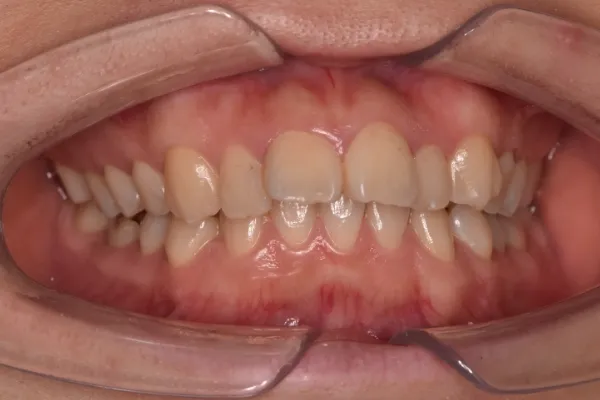

| 診断名・主訴 | 下顎前突、叢生 |

|---|---|

| 年齢・性別 | 23歳・女性 |

| 治療期間・回数 | 3年 |

| 治療に用いた主な装置 | 上顎5,5 下顎4,4 |

| 抜歯部位 | 舌側矯正 |

| 治療費 | 100万円(税抜) |

| リスク・副作用 | 装置による違和感・疼痛・歯肉退縮・歯根吸収・虫歯のリスクなど |

治療前